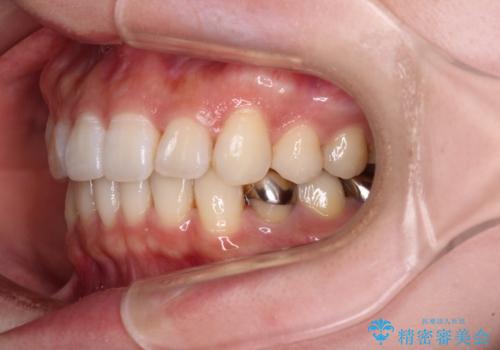

- 前歯のデコボコと深い咬み込みを気にして来院された患者様です。

インビザラインを用いて、前歯の叢生を解消するとともに、深い咬み合わせ(ディープバイト)を改善していくこととしました。

奥歯を後方に直立させることで深い咬み合わせを改善を図り、隠れていた下顎前歯が見えるほどになりました。